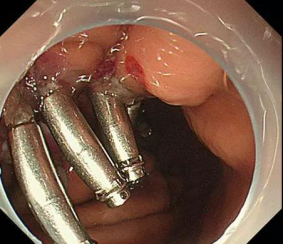

近日,市中医院消化内科在胃镜下通过微创技术,为利州区宝轮镇新街4组余××成功挖出了直径达5公分如土豆大小的“胃间质瘤”,术后恢复良好,痊愈出院。

微创手术切除是首选。如果间质瘤增长快速,说明出现了一定的恶性表现,建议胃镜检查尽早行微创手术切除。

广元市中医院消化内科(内五科)是广元市重点专科,科室近年得到快速发展,拥有高级职称专家5人,博士、硕士研生3人和一大批优秀业务骨干。仅近两年来就添置了奥林巴斯290超声内镜、放大内镜、治疗内镜及奥林巴斯290高清肠镜系统等系列尖端设备,形成了强大的综合实力。年开展胃肠镜诊疗10000余例。近年来率先成功开展了“人工肝支持系统治疗肝衰竭”、“腹水超虑浓缩回输术治疗肝硬化腹水”、“食管支架植入术”、“食管静脉曲张套扎术”、 “消化道早癌筛查”、“食管胃底静脉曲张硬化治疗”、“内镜下粘膜切除术(EMR)”、“内镜下粘膜剥离术(ESD)”、“内镜经粘膜下隧道肿瘤切除术(STER)”、“经口内镜下肌切开术治疗贲门失迟缓症”、“超声内镜”等技术,免除了患者做大手术带来的痛苦,因强大的技术综合实力享誉川北及陕甘毗邻地区。